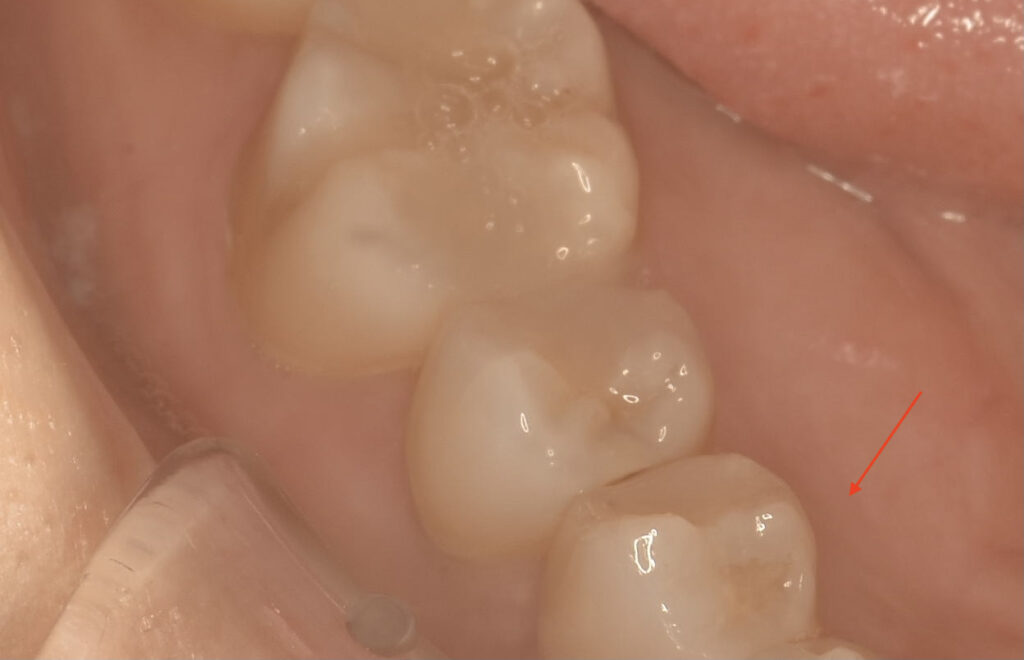

口腔内を見た状態 キレイにレジンが詰められていますね

上の写真は舌側(内側)からみたところ